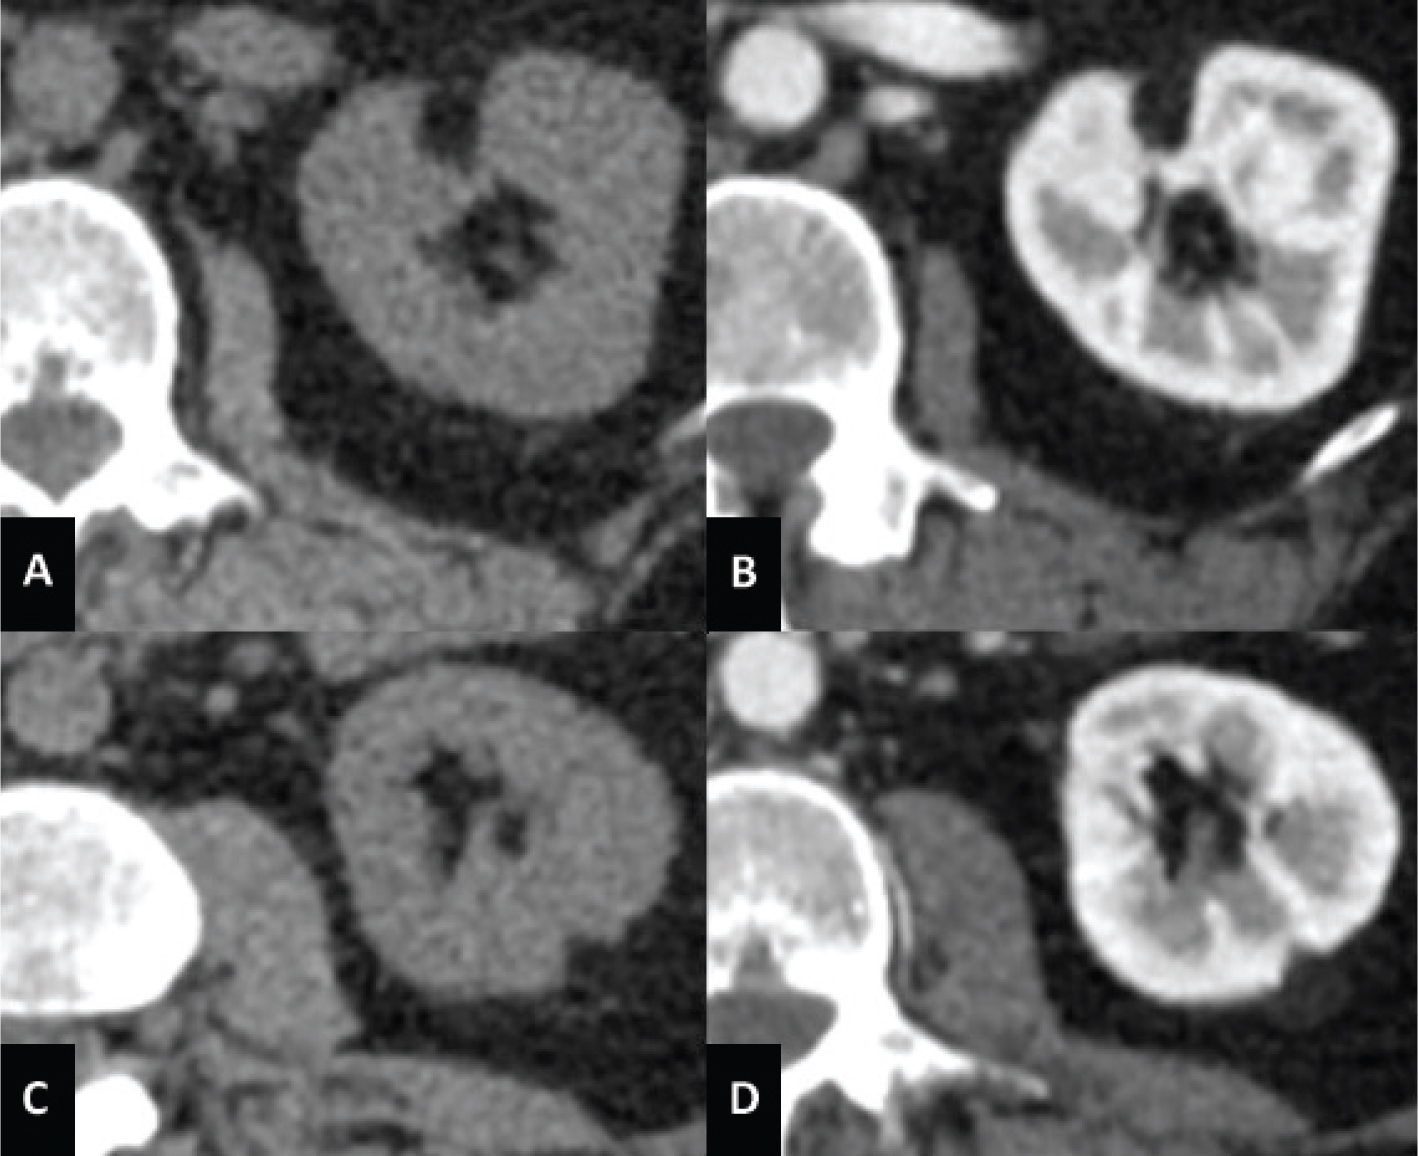

Fig 2

Figure 2. MRI axial scan of the abdomen shows two AMLs of the left kidney. (A) Opposed-phase shows the characteristic India ink artifact of the AMLs. (B) AMLs appear hyperintense on T2-weighted images and (C) hypointense on T2-weighted images with fat suppression. (D) T1-weighted image with fat suppression shows contrast enhancement of the AMLs.